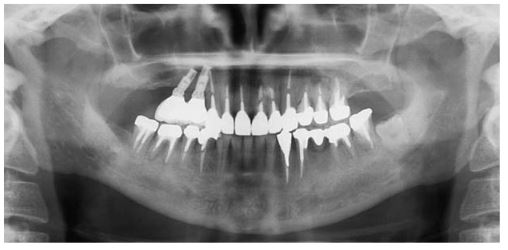

インプラントは適切な位置への埋入が不可欠な手術。歯科用CTで立体的に状態を確認したりすることは、より確実な治療成果を出すためには必要なもの。また術中の患者さんの状態を監視するシステムはあるかなど、外科手術に必要な設備が整っているかをチェック。